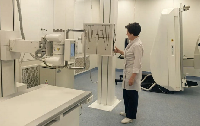

На рабочем месте производится обучение работе на Вашем оборудовании.

Любого доктора можно быстро подготовить как рентгенлаборанта и дать необходимые знания для оценки рентгенограмм.

Изучение проблемы низкого качества рентгенограмм на Вашем оборудовании.